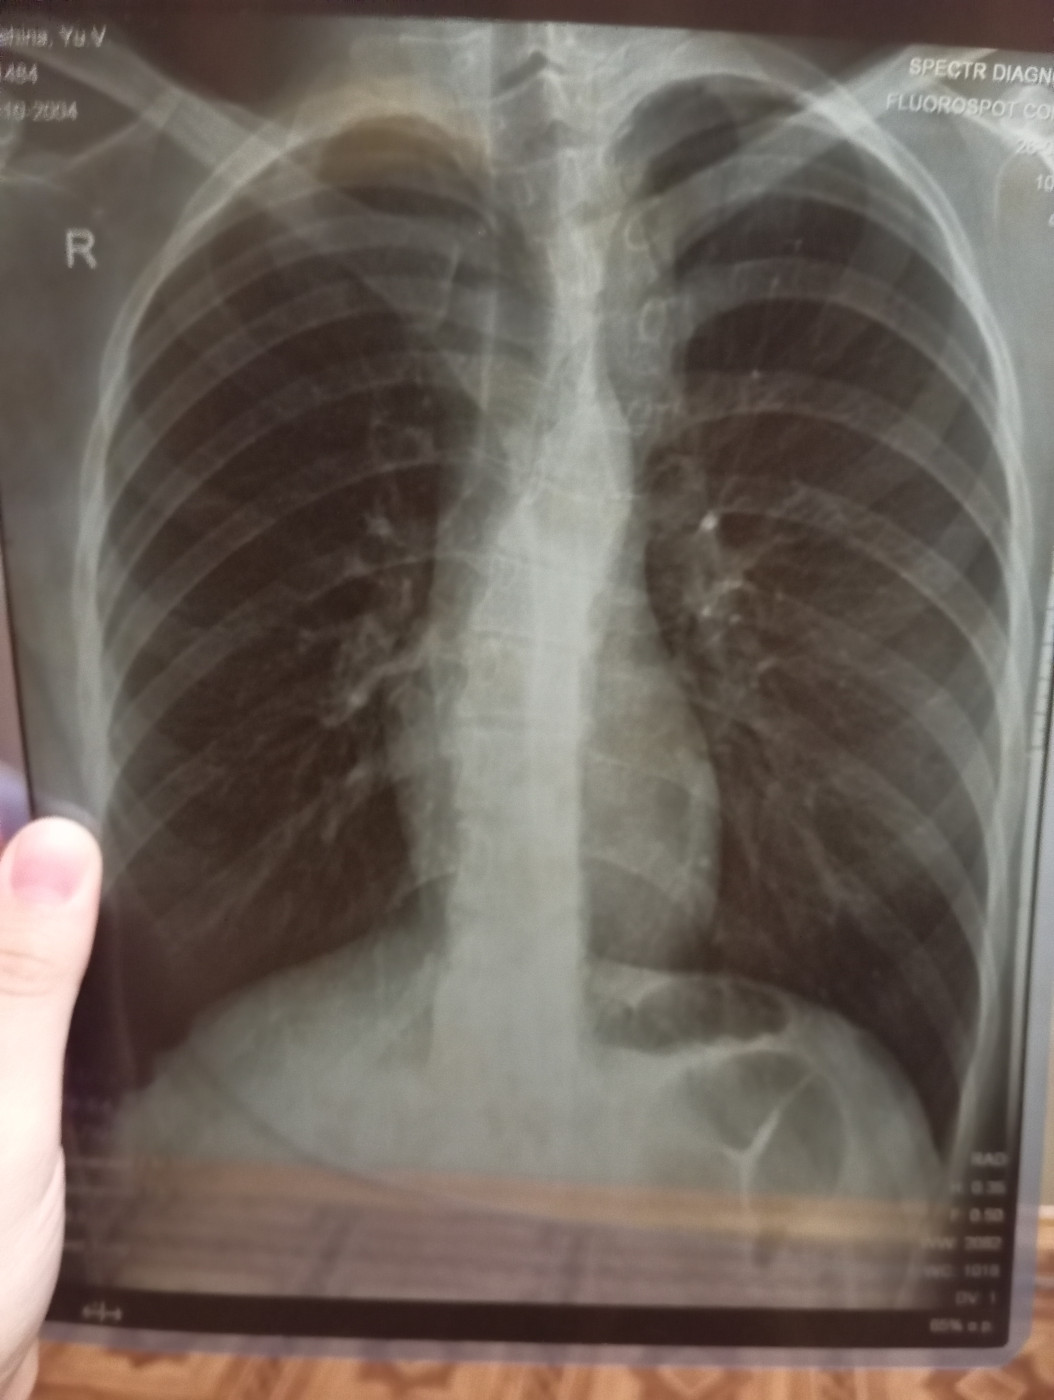

Наличие туберкулёза есть или нет?